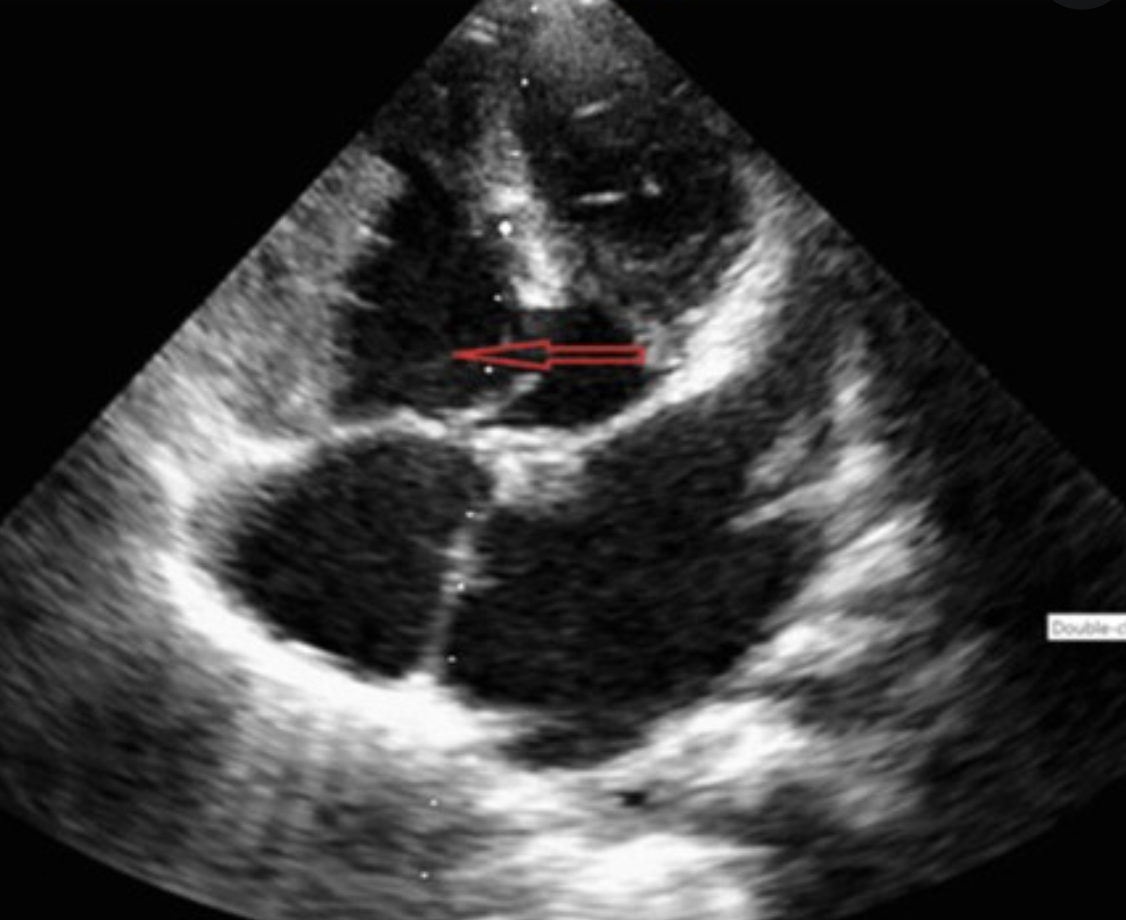

23

Q

What is this?

A

Subarterial VSD

24

Inlet VSD